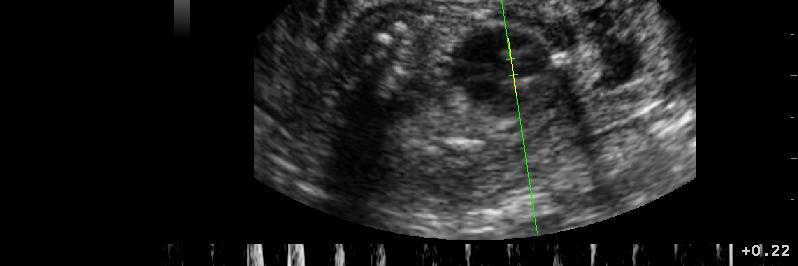

Auch in der Veterinärmedizin wird das schonende Verfahren der Ultraschalldiagnostik zunehmend eingesetzt. Wir verwenden es im Bereich der Abdominal- und Trächtigkeitsdiagnostik .